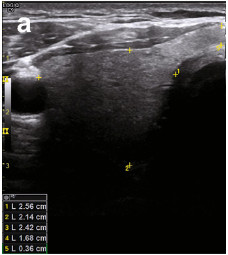

Normal thyroid measurements + volume

A

• <6cm long

• 1.8 cm AP

• <6mm isthmus thickness

• <18ml women

• <25ml men

To measure: 1 caliper in long, 2 calipers in trans